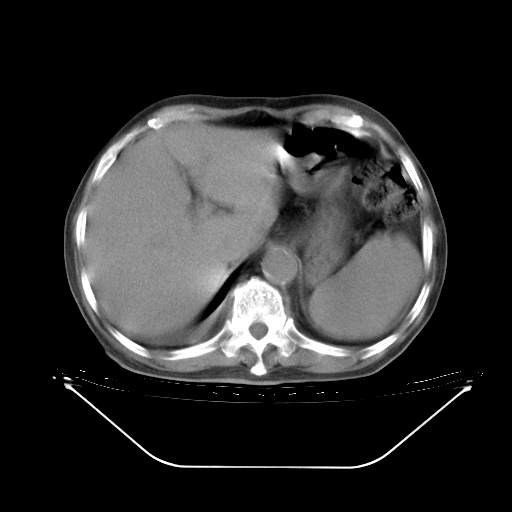

胸腹部CT,诊断意见:左上肺叶钙化灶、左侧胸膜局限性增厚并钙化、胆囊炎。描述部分肺组织呈磨玻璃样改变。

5月9日肺部CT(在4月27日齐鲁医院肺部CT描述部分肺组织磨玻璃样改变,12天后肺组织广泛磨玻璃样改变)

大致读了系列胸部CT:纵隔窗无明显异常,肺窗:从4、27至今:主要是双肺中下野外带可见毛玻璃样改变,目前处于急性肺泡炎阶段,至于原因考虑1、结替组织或胶原血管性疾病所致?2、恶性疾病如恶组在肺部所致的表现或细支气管肺泡癌?3、药物或其它原因如肺蛋白沉着症所致肺泡炎目前不太可能?总之,明天就去请我院的呼吸科、感染科、血液科和临免专家会诊哈。